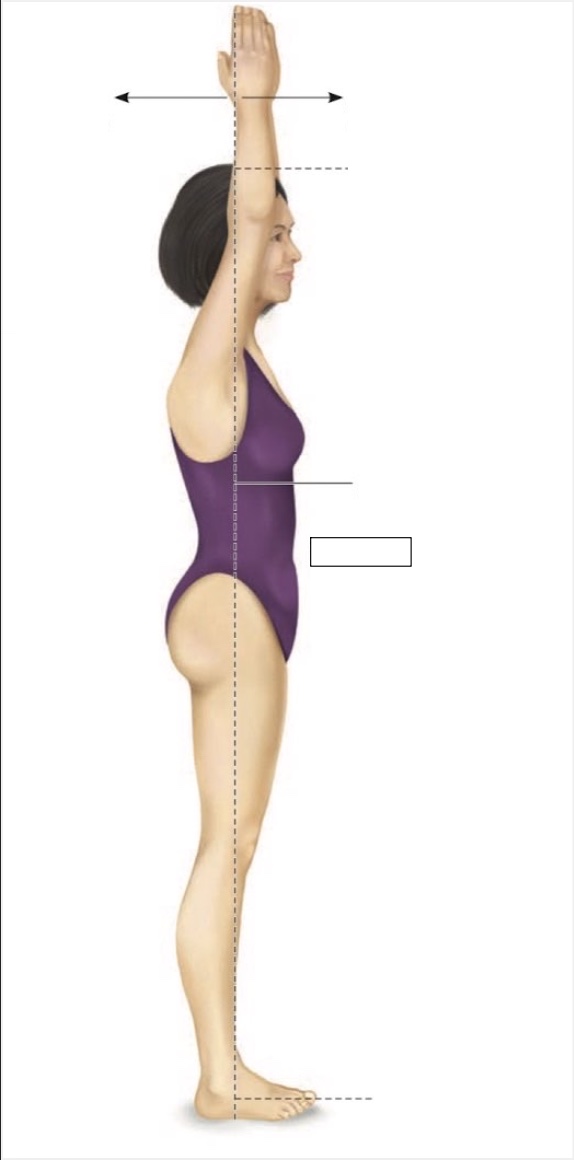

Superior

Inferior

Midline

Proximal

Distal

Palmar

Medial

Lateral